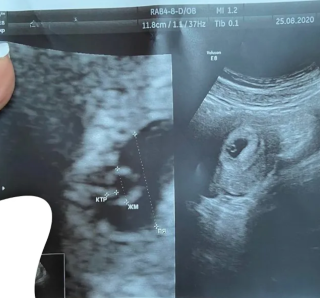

Через чотири місяці після другого етапу оперативного лікування у пацієнтки виникла затримка менструації.

Причиною стала маткова вагітність.

Вагітність перебігала без ускладнень, попри те, що на той момент Інні вже виповнилося 39 років.